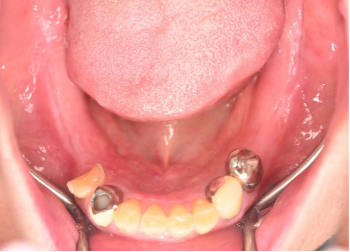

Before

▼初診時に使用していた部分入れ歯を装着したところ

▼インプラント埋入前